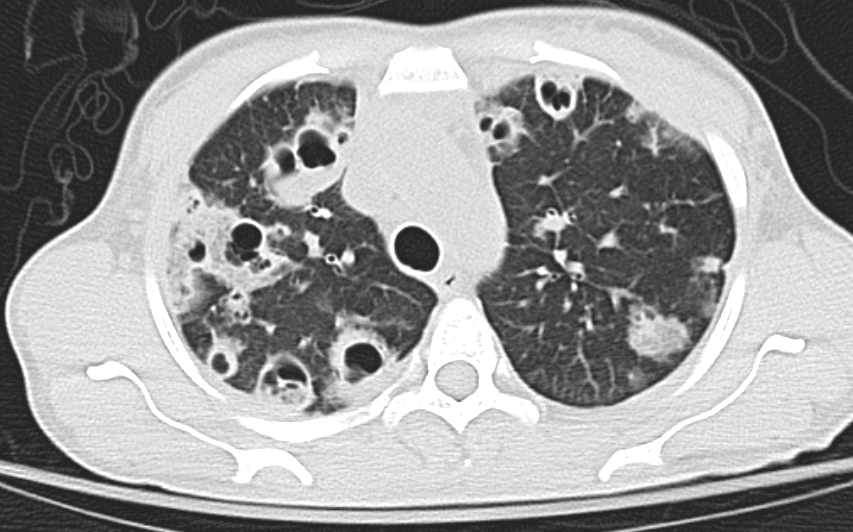

A 49-year-old man presented to the emergency department for a chronic cough with intermittent hemoptysis, fever, and flank pain. He denied any history of tuberculosis exposure or smoking.

11/09/2019